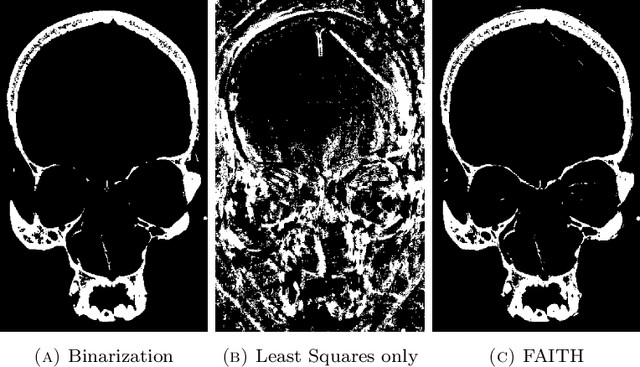

Thresholding is the most widely used segmentation method in volumetric image processing, and its pointwise nature makes it attractive for the fast handling of large three-dimensional samples. However, global thresholds often do not properly extract components in the presence of artifacts, measurement noise or grayscale value fluctuations. This paper introduces Feature-Adaptive Interactive Thresholding (FAITH), a thresholding technique that incorporates (geometric) features, local processing and interactive user input to overcome these limitations. Given a global threshold suitable for most regions, FAITH uses interactively selected seed voxels to identify critical regions in which that threshold will be adapted locally on the basis of features computed from local environments around these voxels. The combination of domain expert knowledge and a rigorous mathematical model thus enables a very exible way of local thresholding with intuitive user interaction. A qualitative analysis shows that the proposed model is able to overcome limitations typically occuring in plain thresholding while staying efficient enough to also allow the segmentation of big volumes.